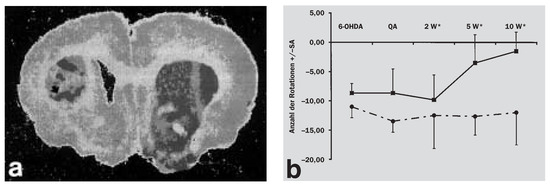

Aktuelle Aspekte zur Diagnostik und Therapie der Multisystematrophie

by Gregor K. Wenning, Z. Puschban, K. Seppi and C. Scherfler

Swiss Arch. Neurol. Psychiatry Psychother. 2000, 151(4), 150-158; https://doi.org/10.4414/sanp.2000.01166 - 1 Jan 2000

First described in 1969 by Graham and Oppenheimer, multiple system atrophy (MSA) is increasingly recognised as distinctive neurodegenerative disease. Clinically, it is characterised by autonomic failure, parkinsonism, cerebellar ataxia and pyramidal signs in any combination. The motor disorder is dominated by parkinsonism in [...] Read more.

First described in 1969 by Graham and Oppenheimer, multiple system atrophy (MSA) is increasingly recognised as distinctive neurodegenerative disease. Clinically, it is characterised by autonomic failure, parkinsonism, cerebellar ataxia and pyramidal signs in any combination. The motor disorder is dominated by parkinsonism in 80% of patients (MSA-P) or by cerebellar ataxia in the remaining 20% (MSA-C). Although the clinical syndrome is often highly characteristic in advanced stages clinicopathological and epidemiological data indicate that multiple system atrophy is underdiagnosed in movement disorders clinics as well as in the general population. It remains to be determined whether the recent consensus diagnostic criteria for multiple system atrophy (Gilman et al. 1998) will improve patient recognition. Physical manoeuvres and/or drug therapy may considerably improve orthostatic dysfunction and urogenital complaints, unfortunately these measures are not always implemented. The motor disorder of multiple system atrophy cannot be treated effectively in most patients although transient relief may be obtained by L-Dopa. The latter should therefore be administered to all MSA patients with parkinsonian features. Alternative therapeutic strategies such as neuroprotection and neurotransplantation are currently being explored in experimental multiple system atrophy models. Full article

Show Figures

Figure 1